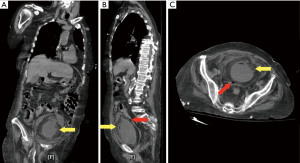

On current presentation, physical examination revealed diffuse abdominal tenderness. A CT scan of the abdomen and pelvis (Figure 1) revealed a bladder wall rupture with bilateral hydronephrosis, in the absence of obstructing urolithiasis. Surgical consultation recommended conservative management, including intravenous fluids, broad-spectrum antibiotics (meropenem and vancomycin), and Foley catheter placement. Urology advised close monitoring of urine output and deferred potential nephrostomy tube placement based on clinical progression. Additional findings included an occipital infarct on CT head and laboratory evidence of leukocytosis, lactic acidosis, and AKI superimposed on her pre-existing CKD.